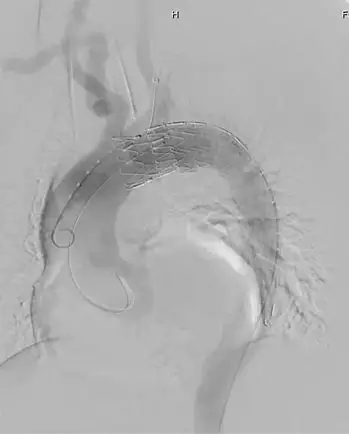

(术前造影)

CT测量显示,近端锚定区直径为30mm,取Ankura™34200支架输送到病变位置,根据Ankura支架大弯侧8字形mark点和加强筋,使其准确锚定于左颈总动脉远端,便于原位开窗。彩神在线网信彩票-彩神通免费版下载-彩神8争霸vlll-彩神购彩购彩大厅-彩神软件陆立根免费版-彩神ll争霸3-彩神ll彩神8-彩神ll争霸彩票-拼搏在线彩神网网页版科技Ankura™主动脉覆膜支架主体的e-PTFE膜设计非常适合原位开窗,其可穿透性佳,用普通的球囊即可扩开,不需要使用切割球囊,且球囊扩开后无撕裂现象,可以降低内漏的发生率。然后采用彩神在线网信彩票-彩神通免费版下载-彩神8争霸vlll-彩神购彩购彩大厅-彩神软件陆立根免费版-彩神ll争霸3-彩神ll彩神8-彩神ll争霸彩票-拼搏在线彩神网网页版Fustar™可调弯鞘和穿刺球囊系统进行左锁骨下动脉开窗,彩神在线网信彩票-彩神通免费版下载-彩神8争霸vlll-彩神购彩购彩大厅-彩神软件陆立根免费版-彩神ll争霸3-彩神ll彩神8-彩神ll争霸彩票-拼搏在线彩神网网页版穿刺球囊系统由球囊和穿刺针组成,充盈的球囊可以使穿刺针保持在分支血管的中央位置。由于此患者左锁骨下动脉与主动脉为锐角弓,穿刺破膜定位比较困难,彩神在线网信彩票-彩神通免费版下载-彩神8争霸vlll-彩神购彩购彩大厅-彩神软件陆立根免费版-彩神ll争霸3-彩神ll彩神8-彩神ll争霸彩票-拼搏在线彩神网网页版Fustar™鞘头端可以调整角度,使其头端与主体覆膜尽量处于直角状态,同时提供足够的支撑力,能够提高开窗成功率和效率。穿刺完成后,采用3mm和8mm的球囊对穿刺破口逐步进行扩张,最后在左锁骨下动脉植入覆膜支架。术后造影显示,支架形态良好,分支血流通畅,无内漏。